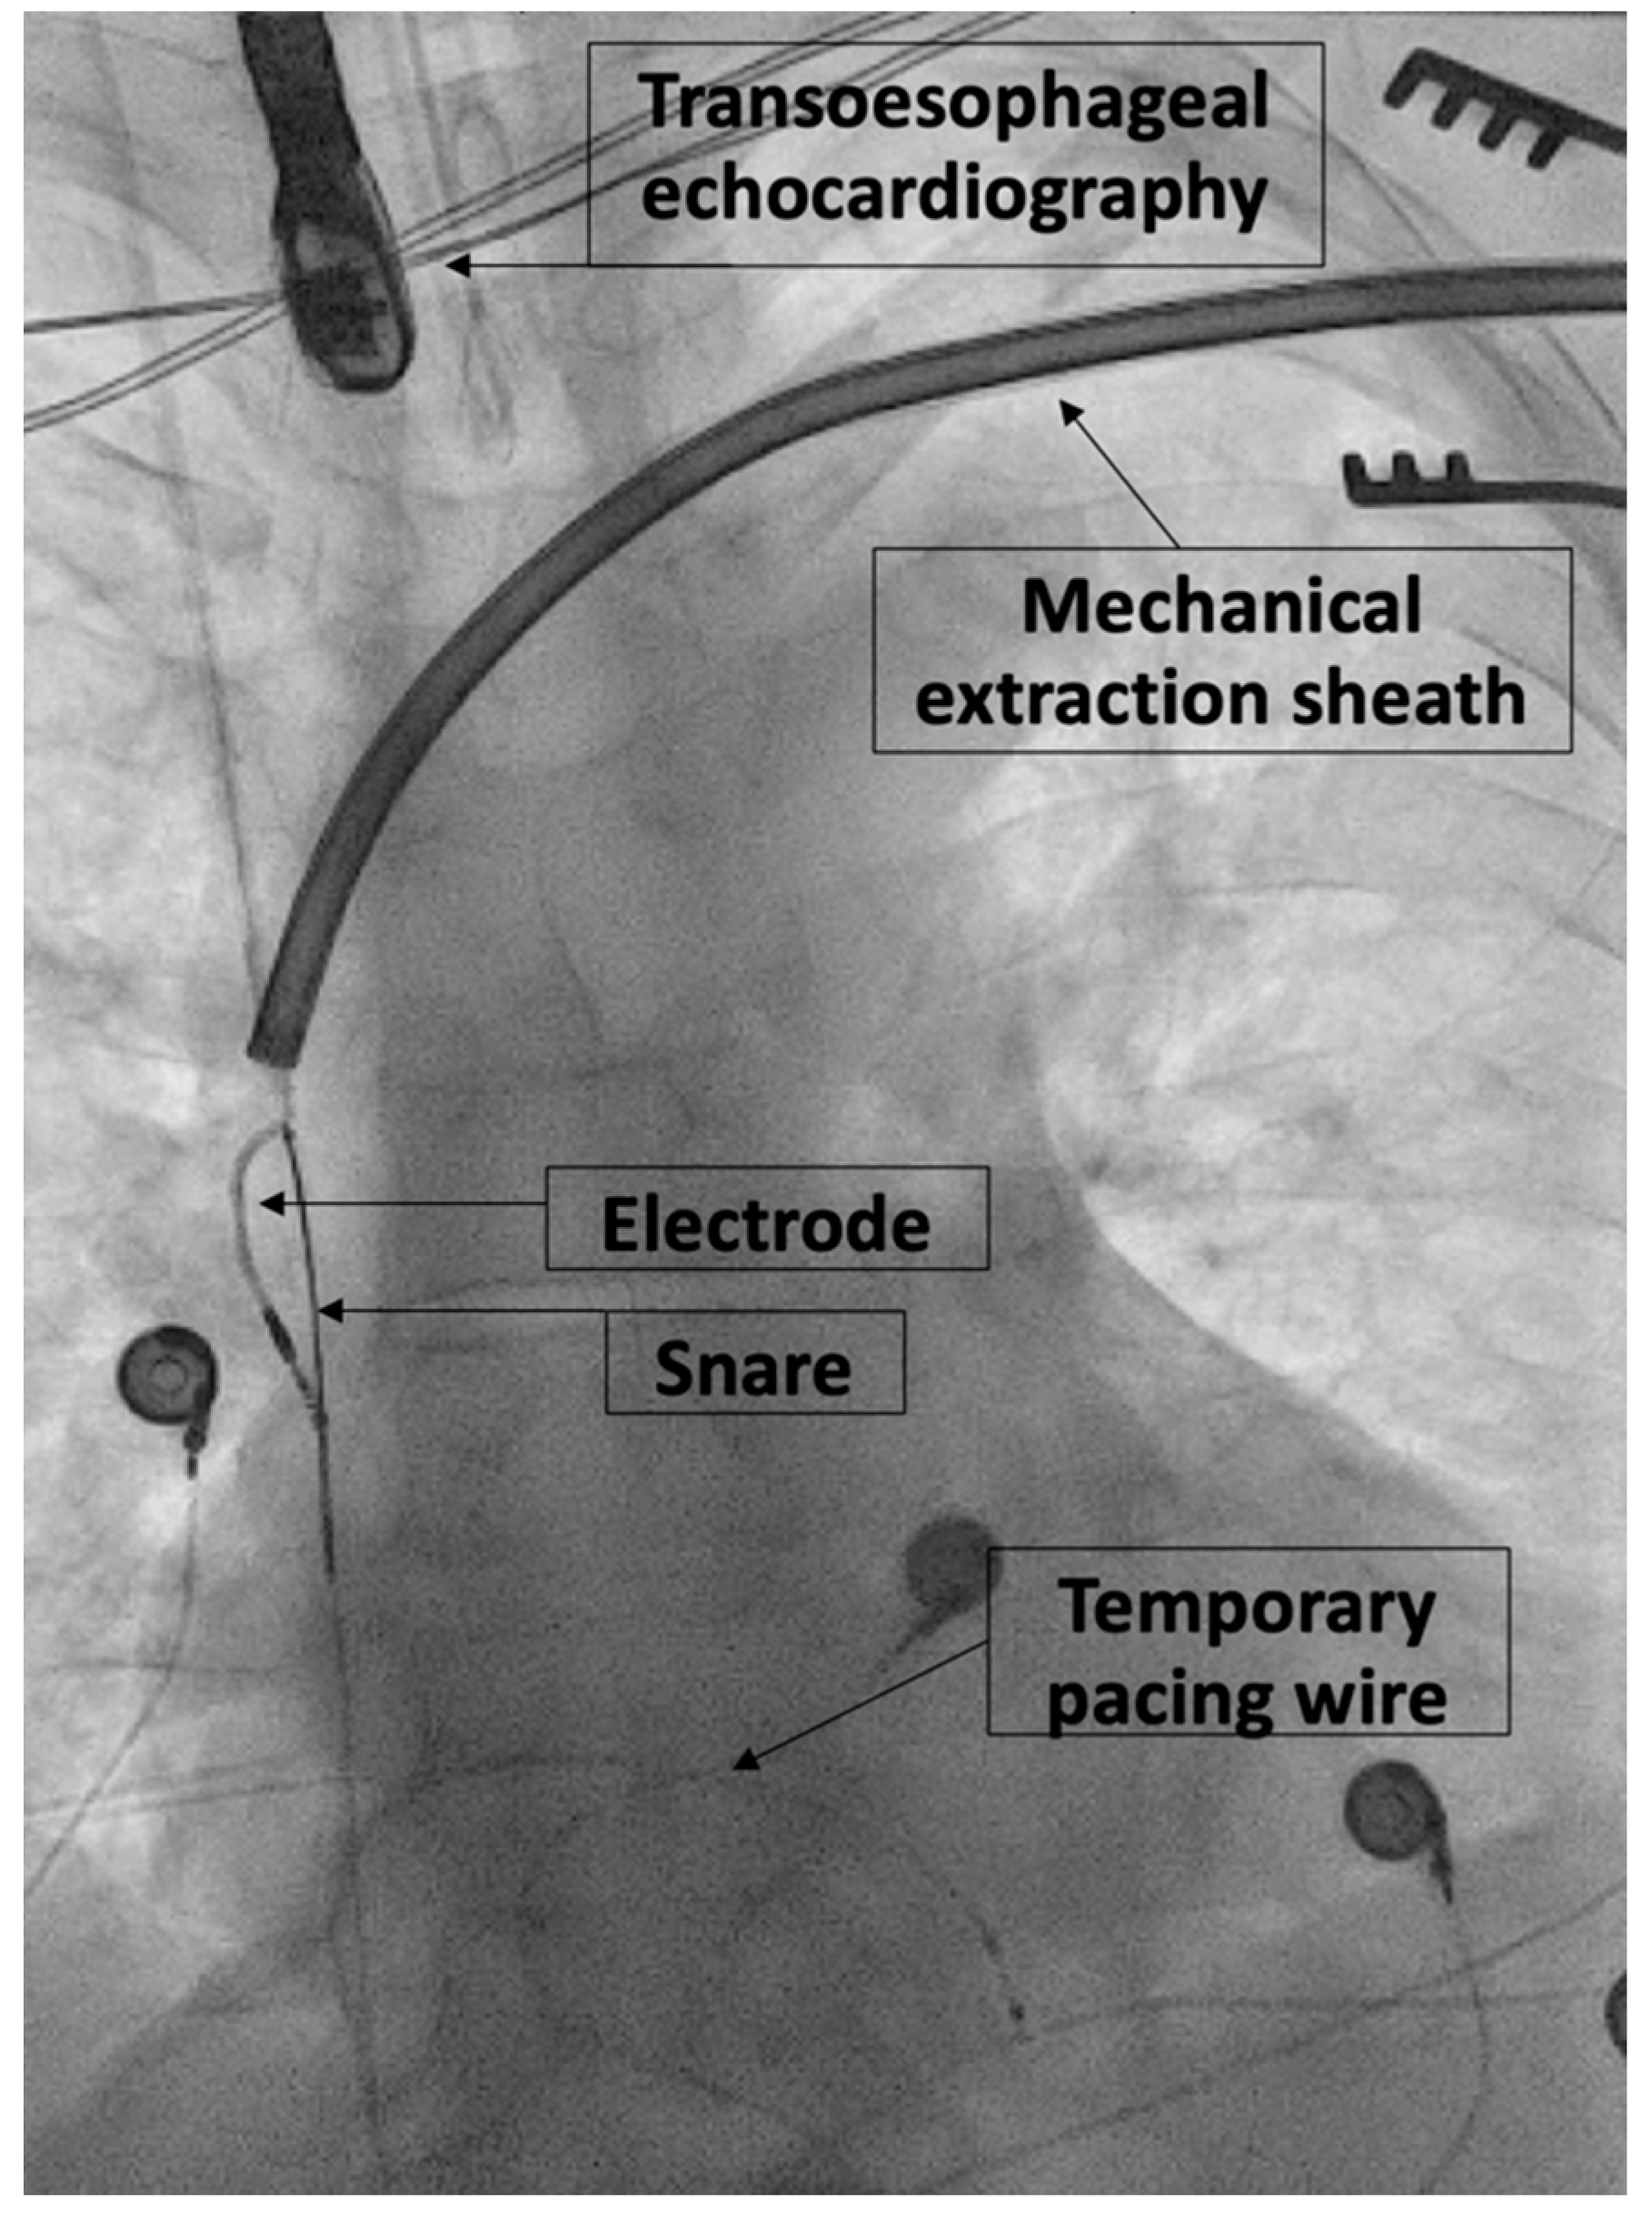

2.2. Extraction Procedure